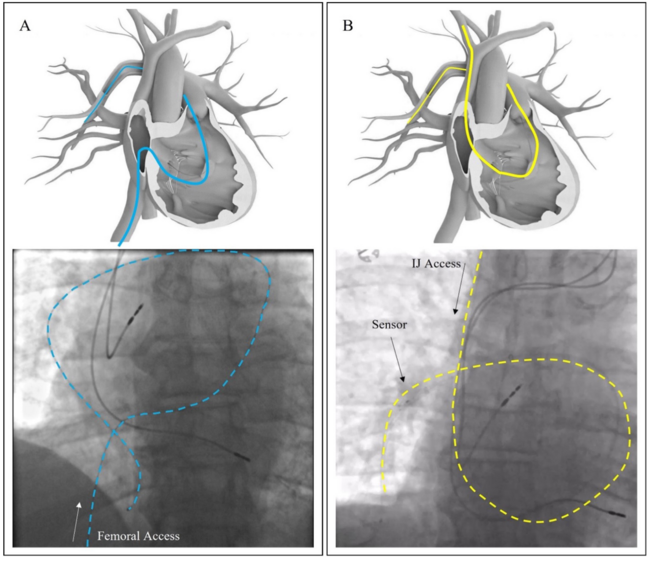

Prior to the presented case, the majority of Cordella implants were completed using femoral vein access with low complication rates comparable to a commercially available PA pressure sensor. Despite many years of using this approach, groin complications remain a significant challenge even when advanced techniques such as ultrasound guidance and micropuncture are employed. Moreover, patient anatomy and/or medical history may pose additional challenges to this technique. As demonstrated in the case presented here, the presence of iliac vein compression prevented femoral access in this case. The IJ access was easily achieved and supported the implantation of the Cordella sensor without challenge. In fact, the anatomy of the RIJ approach formed a “6” as opposed to the more tortuous “S” shape of the femoral approach when traversing the cardiac anatomy (Figure 5). Additional advantages of IJ access include ability to forgo bedrest following the procedure, allowing for faster patient training and discharge, and increasing the throughput in the cardiac catheterization lab, which has potential economic implications.10,11 Most importantly, by having more techniques to implant the Cordella sensor, more patients can benefit from the next generation remote patient management offered by this system. Of note, the currently used protocol fully supports implanters to choose between the femoral and IJ access sites without issuing protocol deviations or requiring medical necessity for either technique.